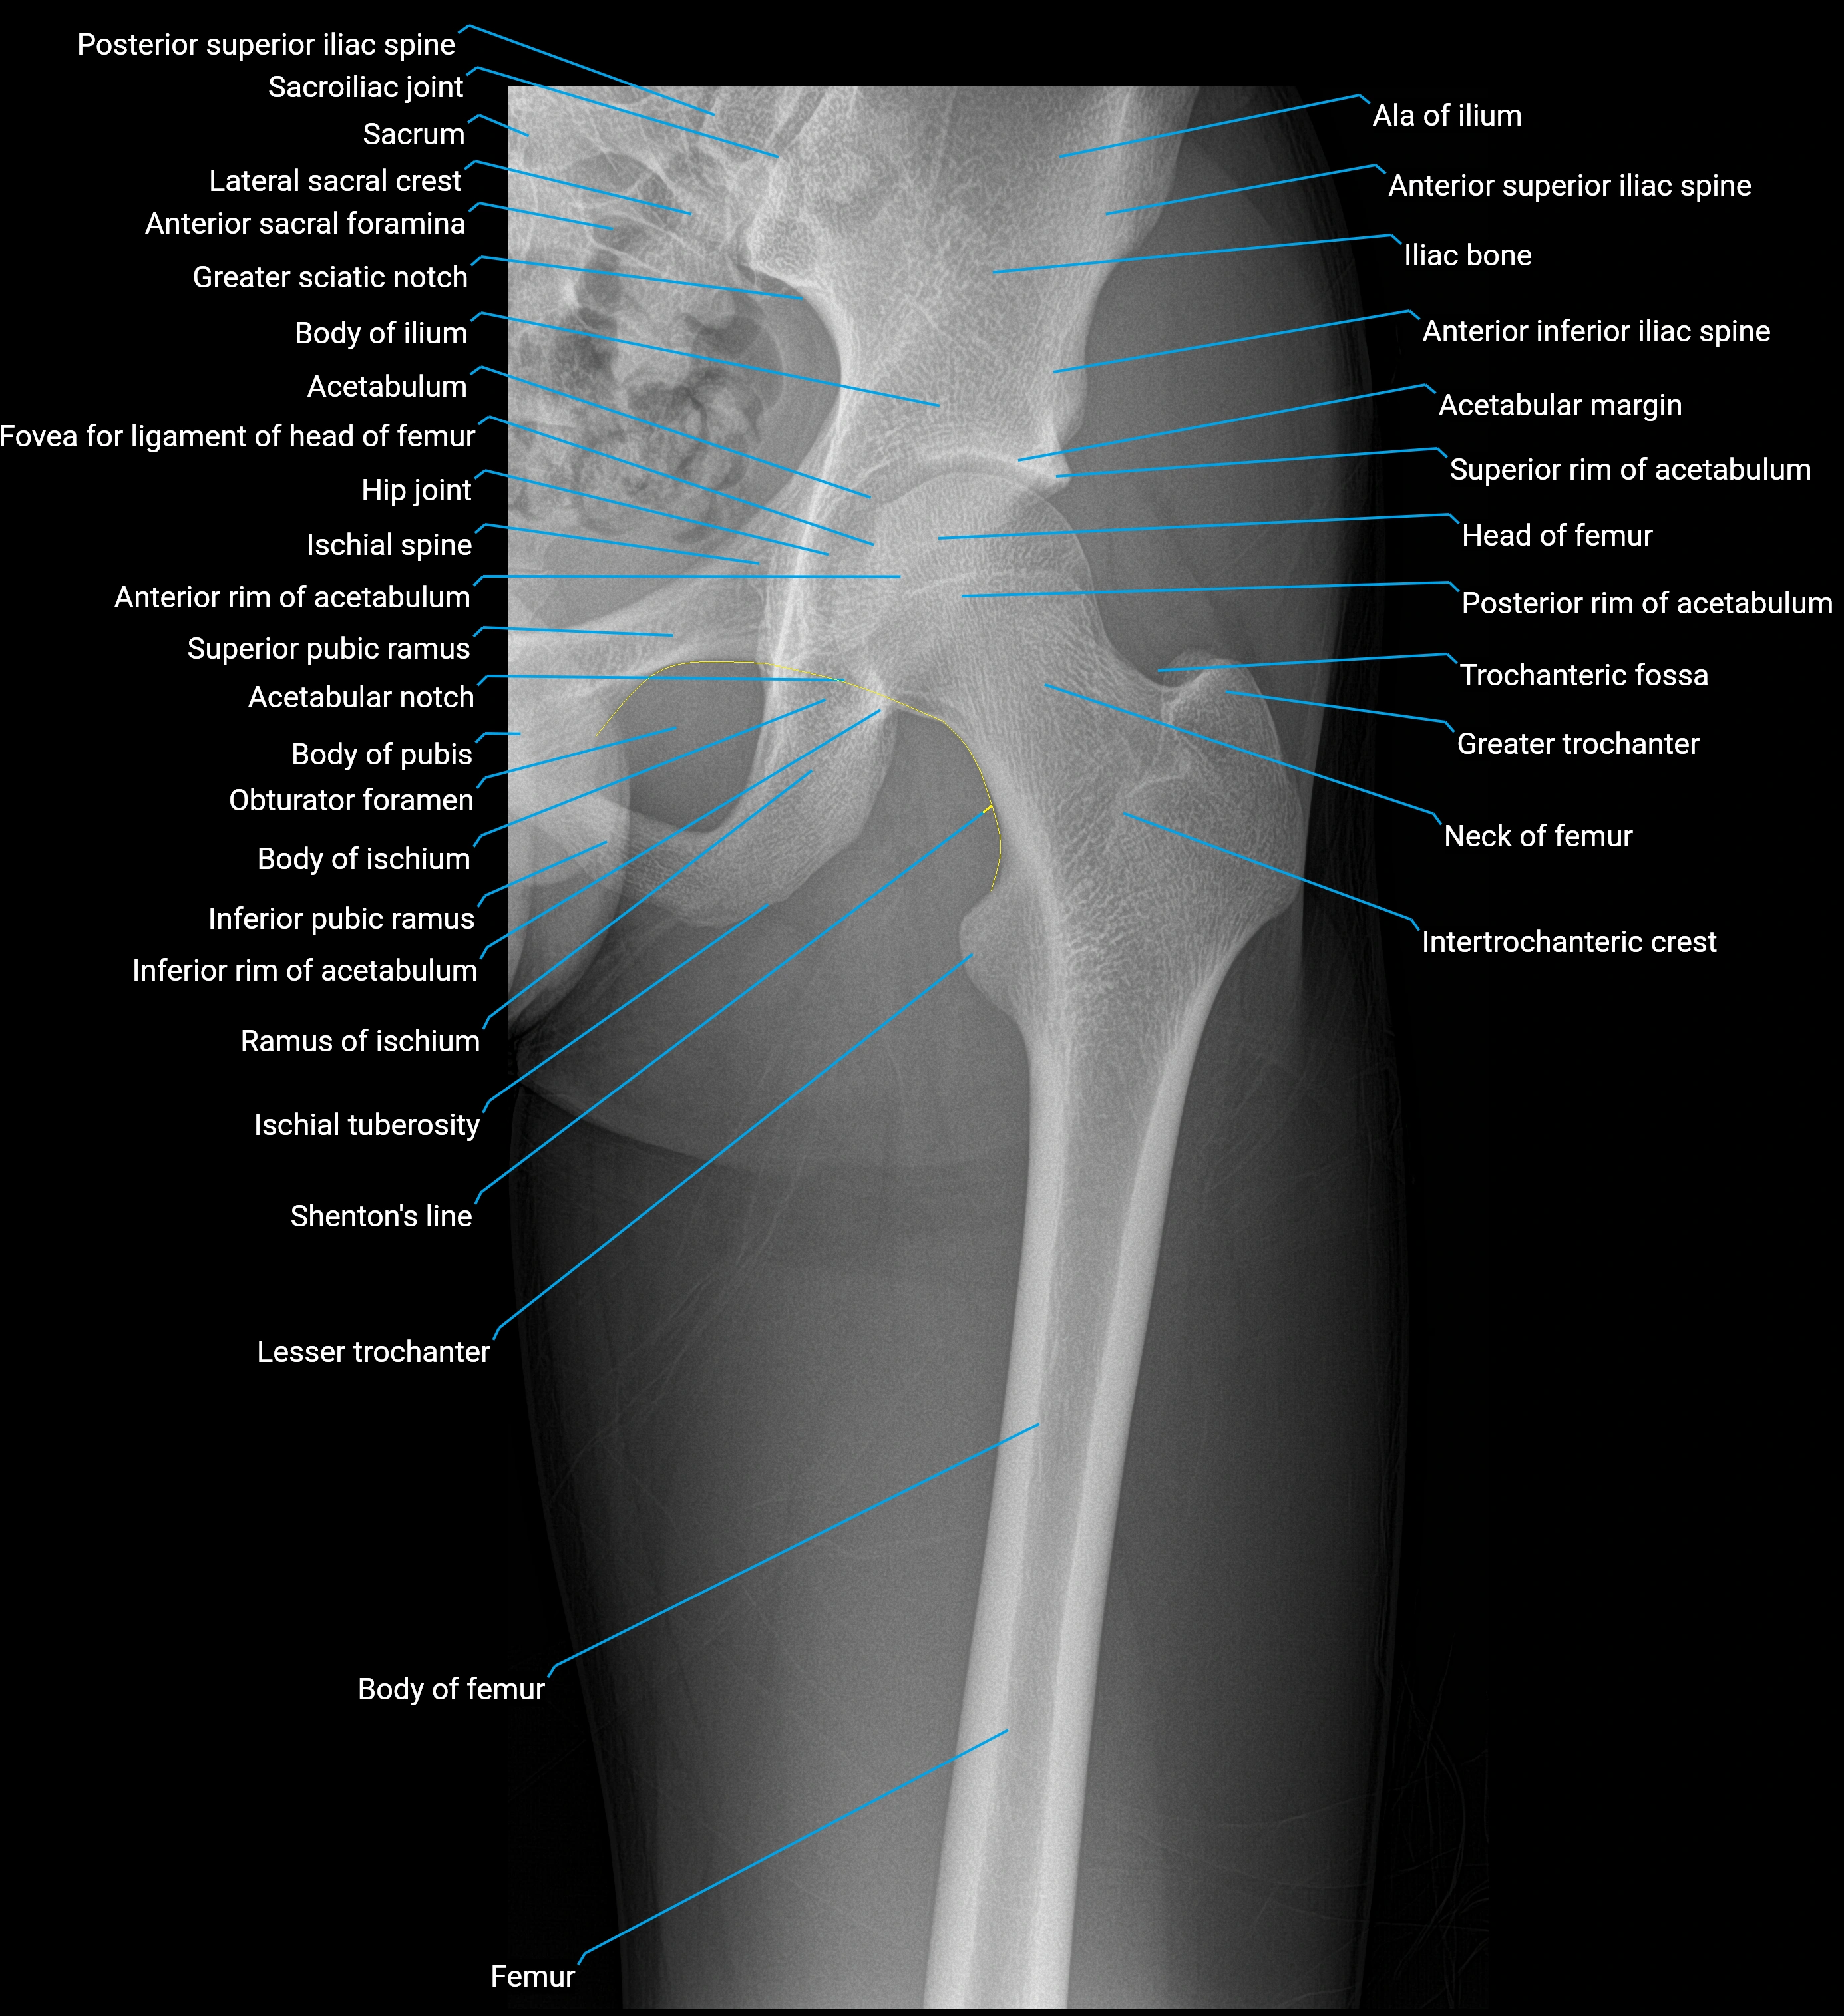

Structure and Relations

• Superior and anterior labrum: thickest portions, stabilizing against anterior dislocation

• Inferior labrum: blends with the transverse acetabular ligament bridging the acetabular notch

• Relations:

• Medial: acetabular articular cartilage

• Lateral: hip joint capsule

• Inferior: transverse acetabular ligament

• Superior: femoral head